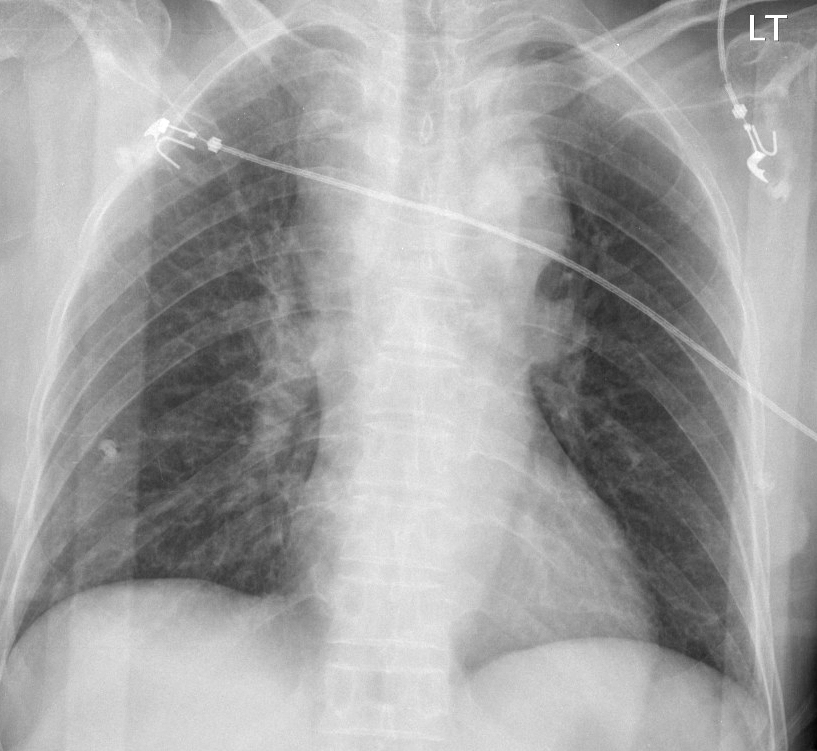

Gallery Blunt Chest Trauma Spine trauma Case 6a

Case 6a